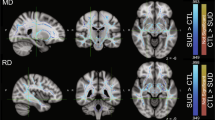

Cocaine dependence is associated with white matter impairments that may compromise cognitive function and hence drug users’ abilities to engage in and benefit from treatment. The main aim of this study was to assess whether white matter integrity correlates with treatment outcome measures in cocaine dependence. Diffusion tensor imaging (DTI) was used to assess the white matter (WM) of 16 treatment-seeking cocaine-dependent patients before 8 weeks of therapy. The measures for treatment outcome were longest self-reported duration of continuous cocaine abstinence, percent of urine screens negative for cocaine, and duration (weeks) of treatment retention. Correlations between treatment outcome measures and DTI parameters (fractional anisotropy (FA), longitudinal eigenvalue (λ1), perpendicular eigenvalue (λT), and mean diffusivity (MD)) were analyzed. Longest self-reported abstinence from cocaine and percent of cocaine-negative urine samples during treatment positively correlated with FA values and negatively correlated with λ1, λT, and MD values across extensive brain regions including the corpus callosum, frontal, parietal, temporal, and occipital lobes, and cerebellum. The findings of an association between better WM integrity at treatment onset and longer abstinence suggest that strategies for improving WM integrity warrant consideration in developing new interventions for cocaine dependence.